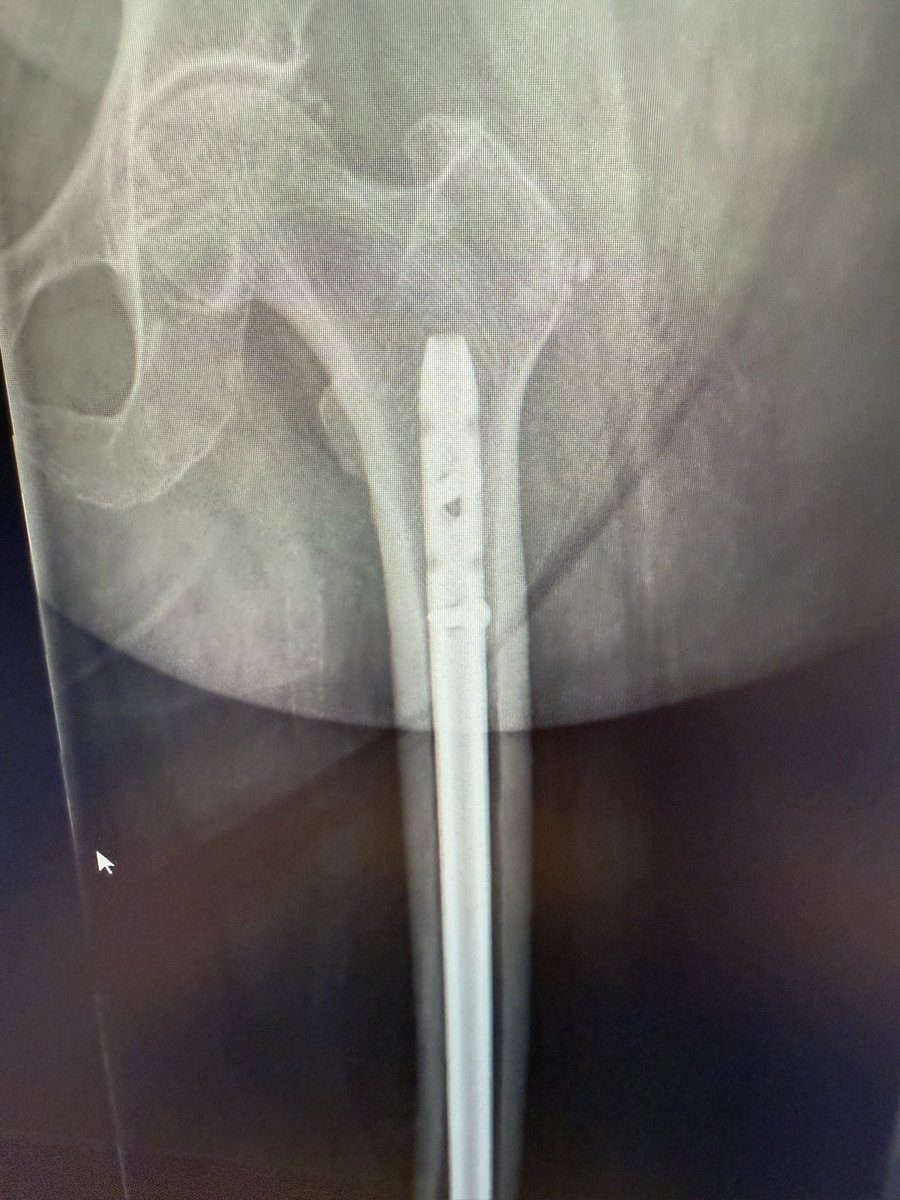

Can you answer our free question of the day? A patient presents to the trauma bay after involvement in a motor vehicle collision. Radiographs obtained in the trauma bay demonstrate a right distal femur fracture, as seen in Figure A. In surgery, the articular block is reduced, and reduction is held with headless compression screws. A retrograde intramedullary nail is then placed. After nail advancement, a varus and recurvatum deformity is noted at the fracture site with intraoperative fluoroscopy, as demonstrated via illustrations in Figures B and C. Placement of blocking screws in which locations (A - H) from Figure B and C would help correct this deformity? 1. B + E 2. A + G 3. B + F 4. C + H 5. D + H QID: 217509 Comment your answer below, then check to see if you got it correct by clicking the link below to see the answer & explanation. bit.ly/3OxP8sP #orthopedics #orthopedicsurgeon #orthopaedics #orthopaedic #orthopedic #ortholife #orthobullets #orthoresidents #orthoresident #orthoresidency #medicalschool #medicalstudent #medstudent #doctor